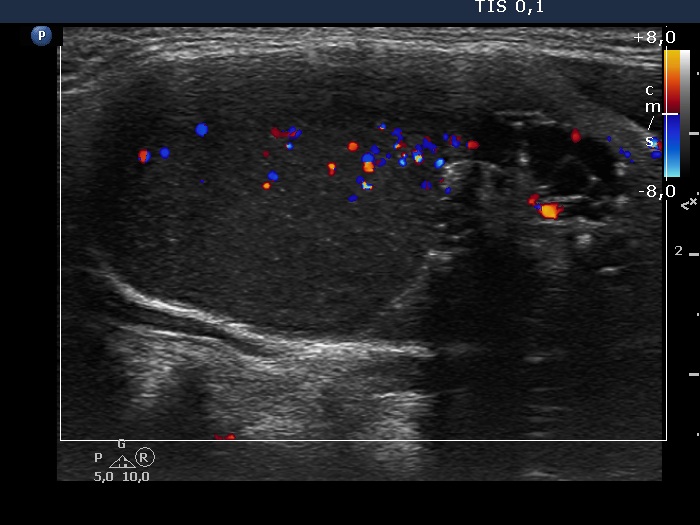

The composition of the nodule - case 126 (ultrasonographic picture 6)

Left lobe, longitudinal scan, color Doppler mode. The pattern of the upper 4/5 of the lesion is deceptive: this part of the nodule contained cystic fluid, so the blue and red spots do not correspond to vessels.